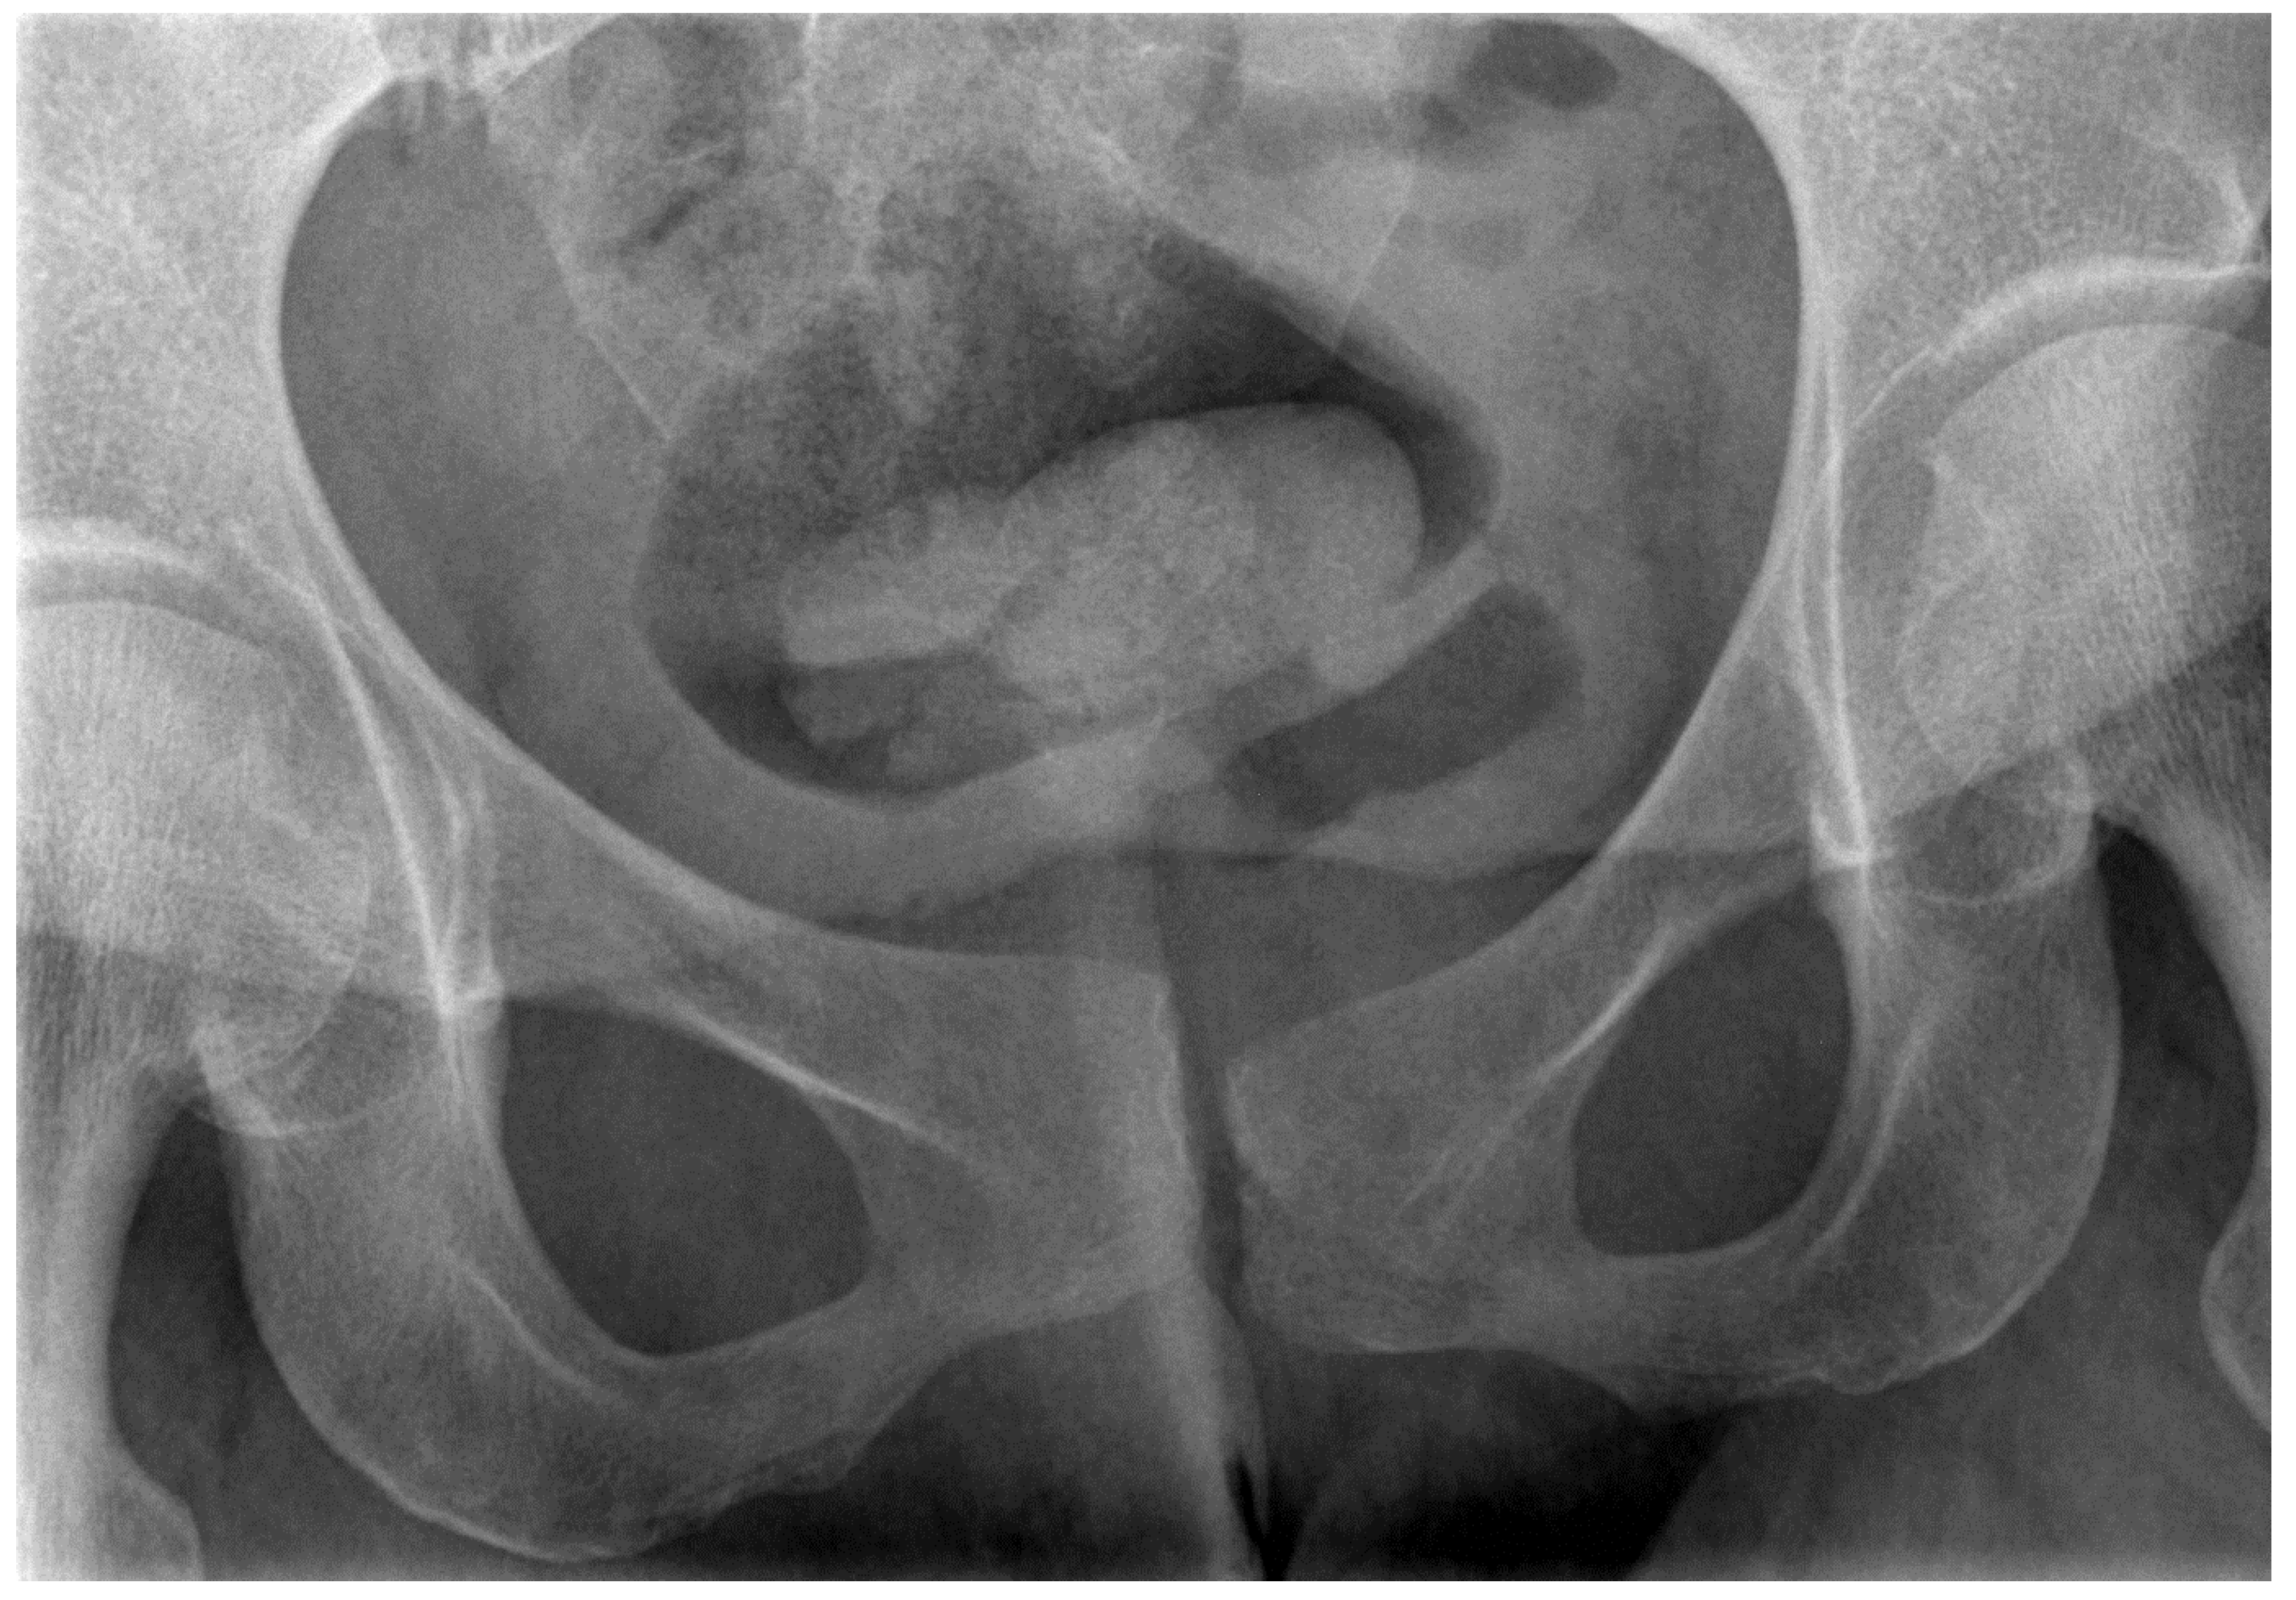

- Van Zwienen, C.M.; Van den Bosch, E.W.; Snijders, C.J.; Van Vugt, A.B. Triple pelvic ring fixation in patients with severe pregnancy-related low back and pelvic pain. Spine 2004, 29, 478–484. [Google Scholar] [CrossRef] [PubMed]